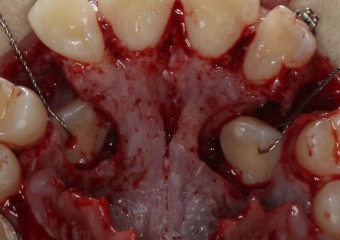

Dentes em tracionamento